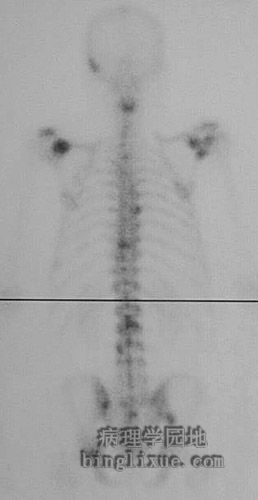

核素扫描显示多个病灶,脊柱周围颜色较深的病灶代表转移性病变。

This nuclear medicine bone scan reveals multiple areas of increased uptake, which are the darker foci, such as in the vertebral column representing metastases.